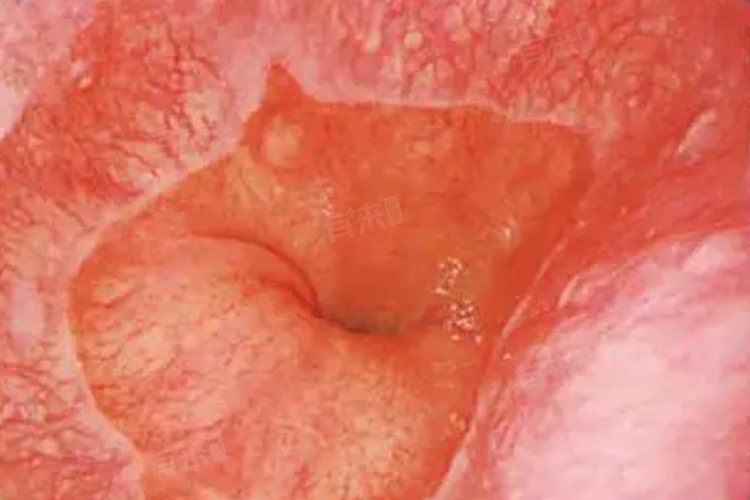

如果是重度异型增生或者已经发展为早期食管癌的Barrett食管患者,手术治疗则是重要的选择。手术方式包括内镜下黏膜切除术或食管切除术等。内镜下黏膜切除术适用于病变局限于黏膜层的情况,通过内镜将病变黏膜完整切除,具有创伤小、恢复快的优点。而食管切除术则用于病变范围较大、侵犯较深的情况,虽然手术创伤较大,但可以彻底清除病变组织,提高患者的生存率。